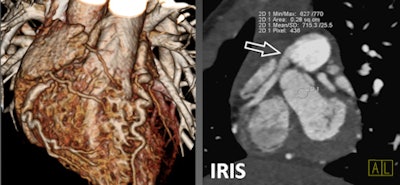

| Above, 4-year-old boy with ARCAPA, or anomalous orgin of the right coronary artery from the pulmonary artery. All images courtesy of Dr. Joseph Schoepf. |

| Iterative reconstruction series. |